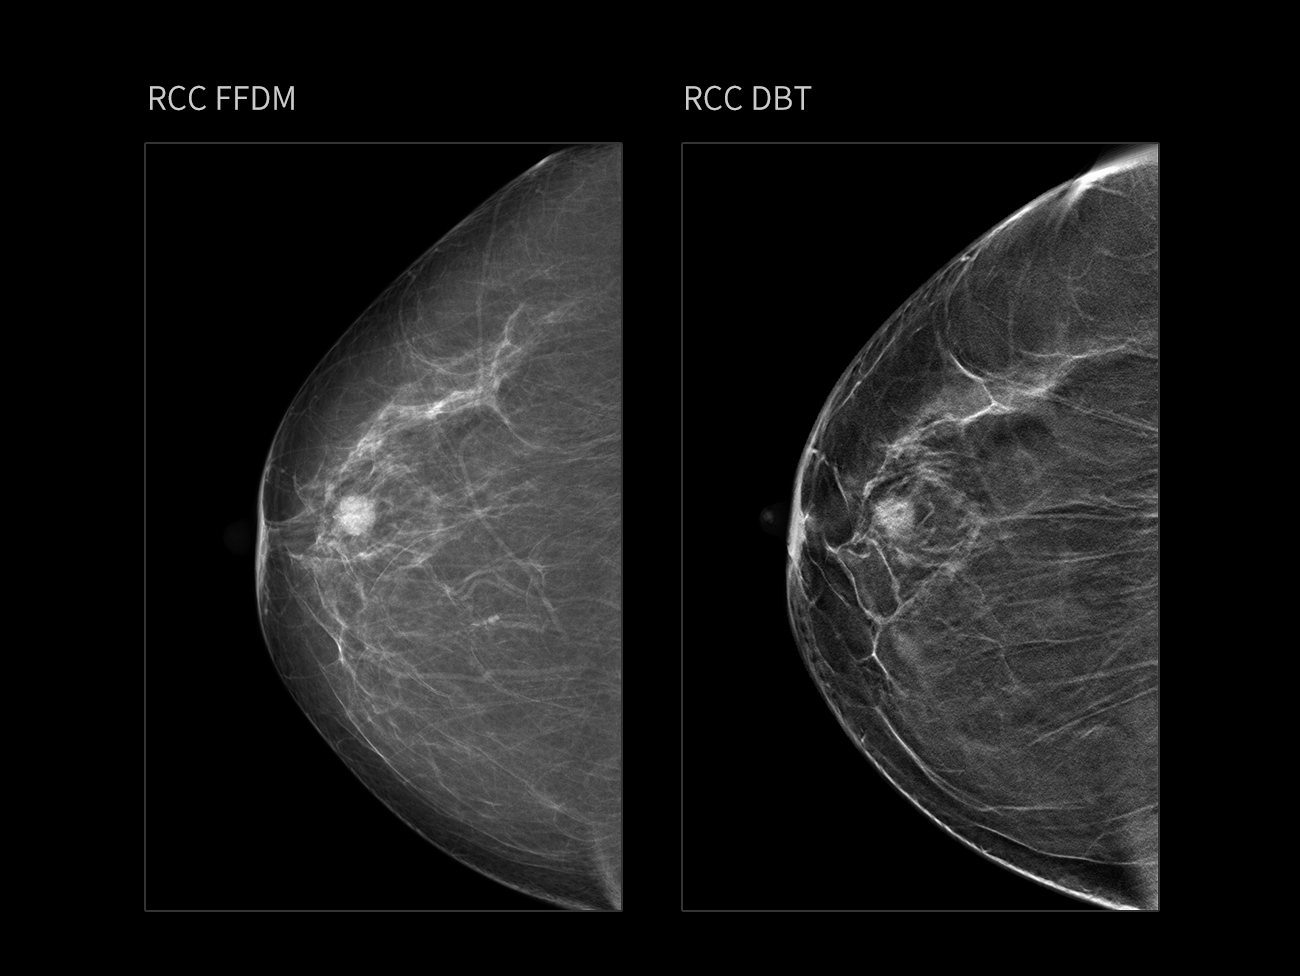

Control automat

Asimetrie

Sân heterogen dens, cu o grosime de 56 mm.

FFDM evidențiază clar o umbră nodulară densă, situată posterior față de mamelonul drept, cu margini parțial clare, lobulație vizibilă și câteva calcificări punctiforme în interior.